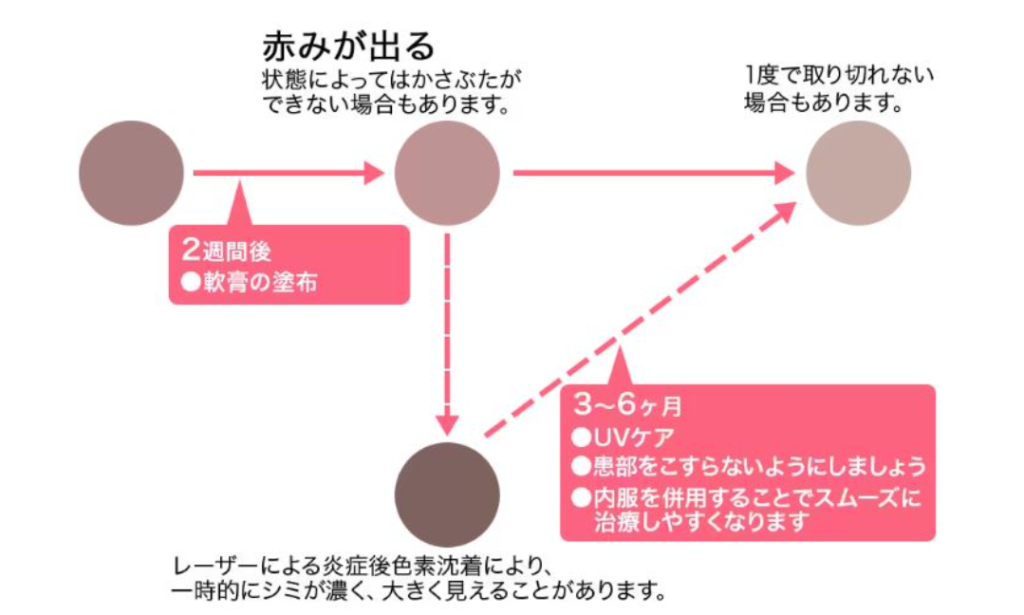

ダウンタイムは、おおよそ以下のように進行します。

ダウンタイムは、おおよそ以下のように進行します。